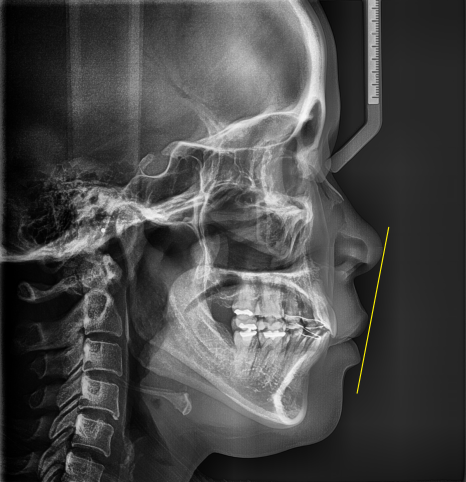

As a result of the diagnosis, there was some skeletal protrusion as well.

The teeth were inclined forward,

and the tension in the soft tissue surrounding the lips made the protrusion look even more pronounced.

In cases like this, it can improve to some extent simply by moving the teeth backward.

we carried out treatment by moving the teeth backward through extraction orthodontic treatment,

and aligning the balance of the lip line and jawline.

The X-ray images also show that the protruded mouth improved,

and when comparing before and after protruding mouth correction, you can see that the jawline and lip line are aligned in a more balanced way.